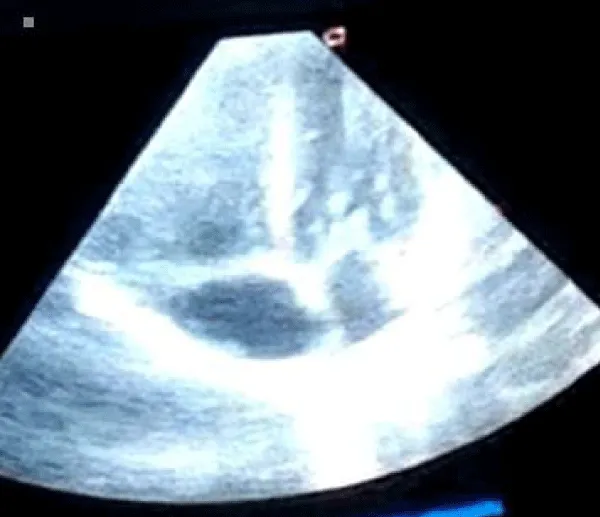

A male neonate delivered at term via SVD to a 24 years old G2P2 mother, who was diagnosed with gestational diabetes at 31 weeks of gestation who had poor glycemic control despite being on subcutaneous insulin and dietary modifications. Mother also had gestational diabetics during her first pregnancy (deranged glycated haemoglobin HbA1c) and claimed her blood sugar normalized after delivery. Her first child was a female and weighed 4.5 kg, alive and well and did not have any immediate neonatal complications. No family history of cardiac diseases. Birth weight of index baby was 4.8 kg (> 95% centile for age) and Apgar scores were 5/7/7 in 1, 5 and 10 minutes respectively. The physical examination showed a macrosomic infant (weight > 95% centile for age), thick upper extremity skin folds, broad shoulder and torso with a relatively smaller head, and plethoric look. He had respiratory distress with peripheral cyanosis. Oxygen saturation (SPO2) was 92% (room air) and urgent random blood sugar (RBS) was 4.6mmol/l. There were no other obvious malformations. Baby was admitted immediately after birth into the special care baby unit (SCBU) of a Federal Medical Centre in southern part of Nigeria for moderate birth asphyxia, severe respiratory distress and macrosomia. Child had persistent respiratory distress while on admission and further cardiac evaluation revealed displaced apex beat with no cardiac murmur. Chest x-ray done showed severe cardiomegaly with bi-ventricular and right atrial enlargements and a cardiothoracic ratio of 68% and oligaemia (Figure 1). Electrocardiography showed evidence of biventricular hypertrophy, right atrial enlargement, sinus tachycardia and occasional premature ventricular complexes (Figure 2). Echocardiography done on the 7th day of life showed severe bi-ventricular hypertrophy with significant narrowing of the left ventricular cavity, marked asymmetrical septal hypertrophy, moderate to severe dynamic subaortic stenosis (Peak gradient 45 mmHg) and left ventricular systolic and diastolic dysfunction (Figure 3). He was commenced on tabs propranolol at 1mg/kg/dose 8hrly and discharged after 5 days with improvement in respiratory distress. He also received oxygen therapy, intravenous fluid and intravenous antibiotics as well as intensive nursing care while on admission. Follow up echocardiography at 6 wks of life showed evidence of remarkable resolution of hypertrophy and improvement in ventricular function (Figure 4).

Download Image

Figure 3: Echocardiography (apical 4 chamber view) showing severe biventricular and septal hypertrophy causing left ventricular outflow tract obstruction and a markedly diminished left ventricular cavity.